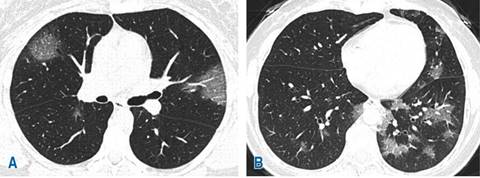

De acuerdo con los hallazgos tomográficos, el patrón predominante en 39% (22) de los casos fue patrón mixto (Figura 1) caracterizado por patrón en vidrio deslustrado, combinado con zonas de consolidación, seguido de patrón empedrado (Figura 2) y patrón en vidrio deslustrado único (Figura 3) con 30% (17) y 29% (16), respectivamente. La localización de las lesiones fue bilateral en 88% (52) de los casos estudiados con mayor involucro de lóbulos inferiores en 55% (31), seguido de afectación en lóbulos superiores en 36% (20). La distribución de las lesiones fue predominantemente subpleural en 48% (27) de los casos estudiados (Figura 4), seguida de afectación con distribución en parches en 20% (11) (Figura 5). En otros hallazgos predominaron las linfadenopatías con 25% (14), seguidas de las atelectasias en 23% (13) (Tabla 2).

Figura 4: Tomografía computarizada de tórax en ventana pulmonar. A y B) áreas extensas en vidrio deslustrado y patrón en empedrado asociado, la afectación es de predominio subpleural bilateral.

Figura 5: Tomografía computarizada de tórax en ventana pulmonar. A y B) Muestran lesiones en vidrio deslustrado, distribución en parches y bilateral.